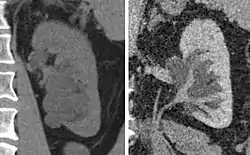

The complex cyst can be further evaluated with doppler ultrasonography, and for Bosniak classification and follow-up of complex cysts, either contrast-enhanced ultrasound (CEUS) or contrast CT is used.[12]